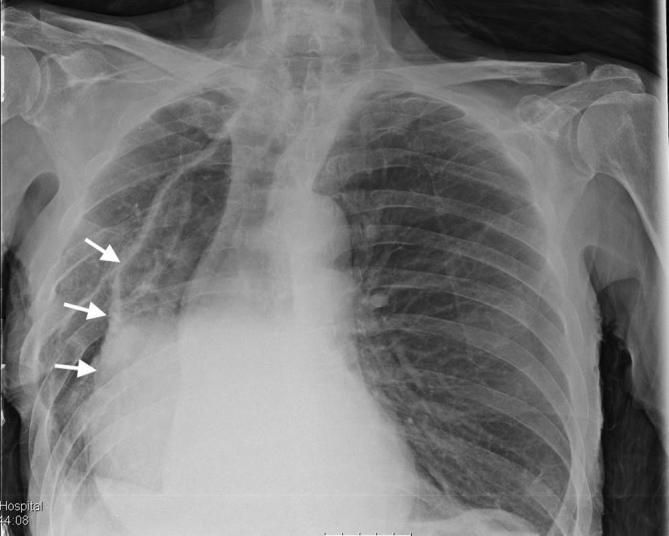

We report the case of an 84-year-old male, who presented with septicaemia, abdominal and back pain. The patient had a background of oesophageal carcinoma and had undergone previous oesophagectomy and gastric pull-up operation 10 years ago. A computerised topography scan demonstrated a probable gastro-vertebral communication with a destructive process at the T8/T9 vertebral level. Further evaluation with MRI clearly showed the tract between the two structures and confirmed the diagnosis of spondylodiscitis at the adjacent spinal level. The patient was resuscitated, treated with intravenous antibiotics and kept nil by mouth. A subsequent gastroscopy demonstrated an eroding gastric ulcer at the enteric opening of the tract between the tubal stomach and the spinal column. The diagnosis was discussed with the patient, his family and the surgical multidisciplinary team. Given the extent of disease and his multiple medical co-morbidities, the decision was made for conservative management and symptom control. This is the first case of a gastro-vertebral communication causing spondylodiscitis to be described in the literature.